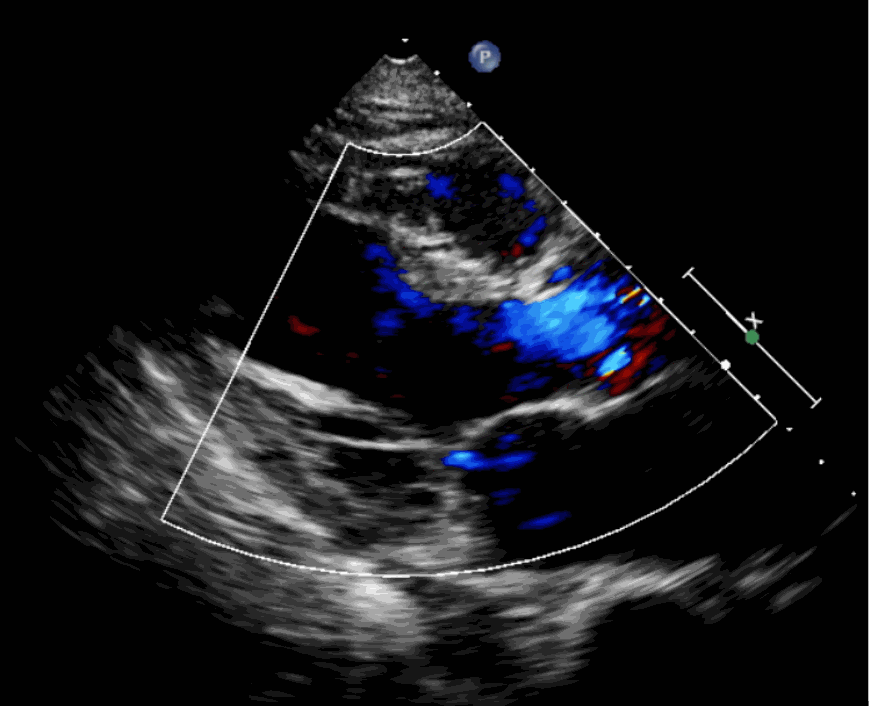

術(shù)前超聲影像圖

該例患者為62歲,女性,因“間歇性心悸、胸悶、氣短、胸痛1年,加重1周”之主訴入院。入院診斷:主動脈瓣重度關(guān)閉不全,二尖瓣、三尖瓣輕度關(guān)閉不全,心功能III級;冠狀動脈粥樣硬化性心臟病。行心臟超聲心動圖提示“主動脈瓣重度關(guān)閉不全;瓣口水平以下左室下壁、后下壁搏幅減低;EF值 0.30,左房、左室大、右房大小正常高限;二尖瓣、三尖瓣關(guān)閉不全;輕度肺動脈高壓(收縮壓42mmHg);主動脈硬化;左室收縮功能重度減低。經(jīng)心血管外科劉洋、楊劍教授、麻醉科陳敏教授及超聲科孟欣教授等專家團(tuán)隊(duì)綜合評估,判定患者為外科手術(shù)高?;颊?。